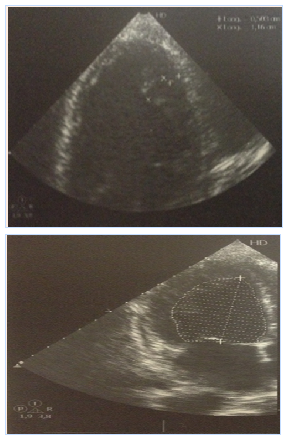

The clinical examination revealed a size 145cm (-3 SD/M.SEMPE) with a total impuberism. The hormonal tests showed a hypergonadotropic hypogonadism. The abdominal CT scan revealed a left hemi-abdominal mass with a large vascular pedicle (supernumerary spleen?) Figure 1. Our patient was followed for cardiac heart failure. The echocardiographic exploration found a left systolic ventricular dysfunction with a septum akinesia and an anterior wall hypokinesia. The left ventricular ejection fraction was 40%. It was therefore a dilated left ventricular non-compaction cardiomyopathy (Figure 2).

Figure 2 Doppler Echocardiography: Appearance of LVNC. Left ventricle systolic dysfunction with anterior, anteroseptal, basal, and median akinesia. High filling pressures EF: 40%.